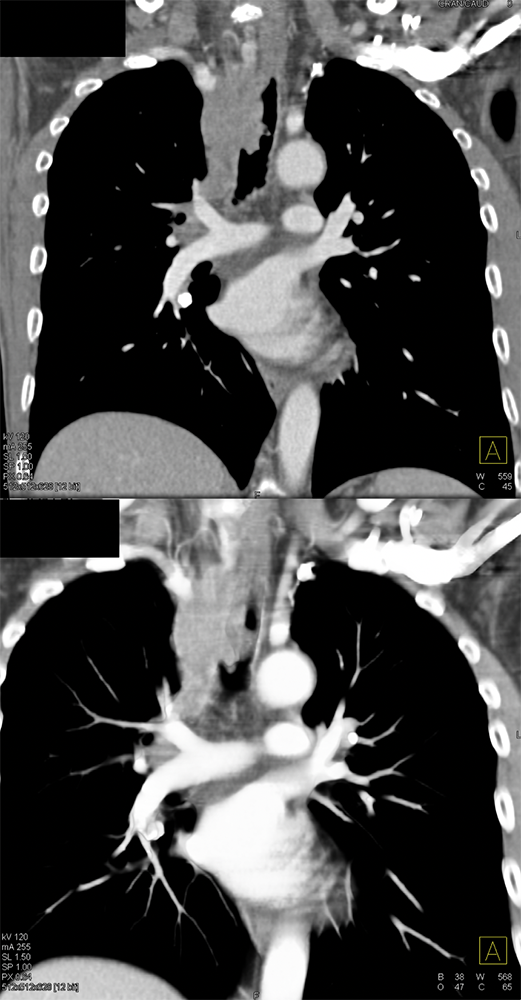

SOB and Hemoptysis ![]() |